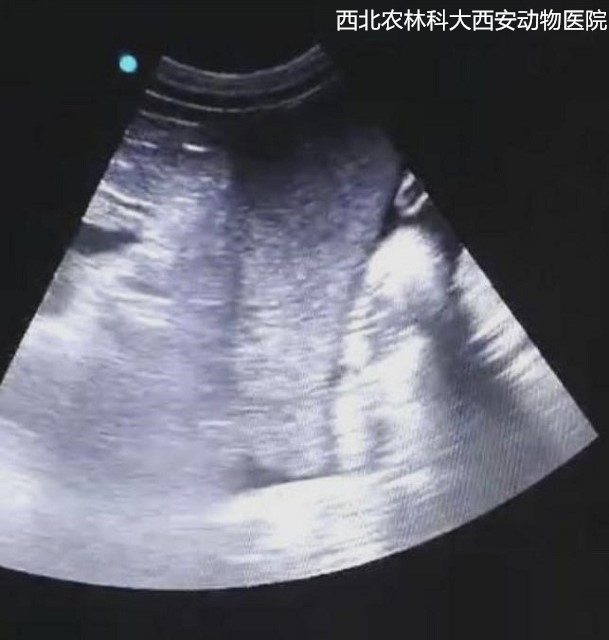

輔助檢查:腹部平片顯示腹腔有一中等密度占位性病變位于左下腹部,腹部器官邊緣銳利程度消失,腹部影像漿膜細(xì)節(jié)不能清晰可見(jiàn),胃和部分腸管積氣,提示腹腔積液、疑似占位待查見(jiàn)(圖1)。為進(jìn)一步診斷腹部占位的性質(zhì),對(duì)患寵進(jìn)行了超聲檢查,結(jié)果顯示腹腔間隙無(wú)回聲,腸管游離,腹腔肝后至膀胱有一非均質(zhì)、低回聲腫物,邊緣圓鈍,輪廓清晰,腫物內(nèi)部偶見(jiàn)低回聲病灶。提示腹腔積液、脾腫大且結(jié)構(gòu)異常,未見(jiàn)扭轉(zhuǎn),待查見(jiàn)(圖2)。

圖二